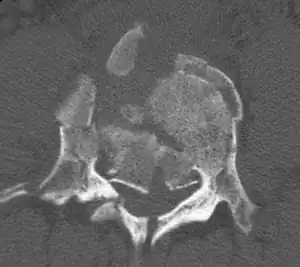

A burst fracture of L4 as seen on CT -

A burst fracture of L4 as seen on CT